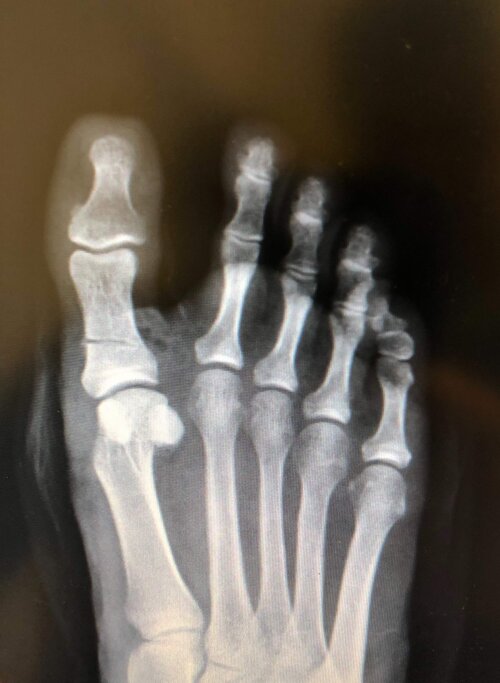

L'indicazione ad effettuare l'intervento chirurgico di correzione dell'alluce valgo è il dolore in corrispondenza del I dito o in corrispondenza della regione plantare delle teste metatarsali ( metatarsalgia ) tale da rendere difficoltosa la deambulazione e l'uso delle normali calzature. L'intervento non si effettua per motivi estetici.Non esiste il laser e l'artroscopia ma si effettua sempre una frattura artificiale

( osteotomia ) dell'osso per effettuare la correzione. Si può utilizzare un accesso mini-invasivo o percutaneo in base alla gravità del caso clinico. L'anestesia è locale o loco-regionale. La deambulazione è immediata con una scarpa apposita. La ripresa dell'attività sportiva avviene dopo tre mesi.